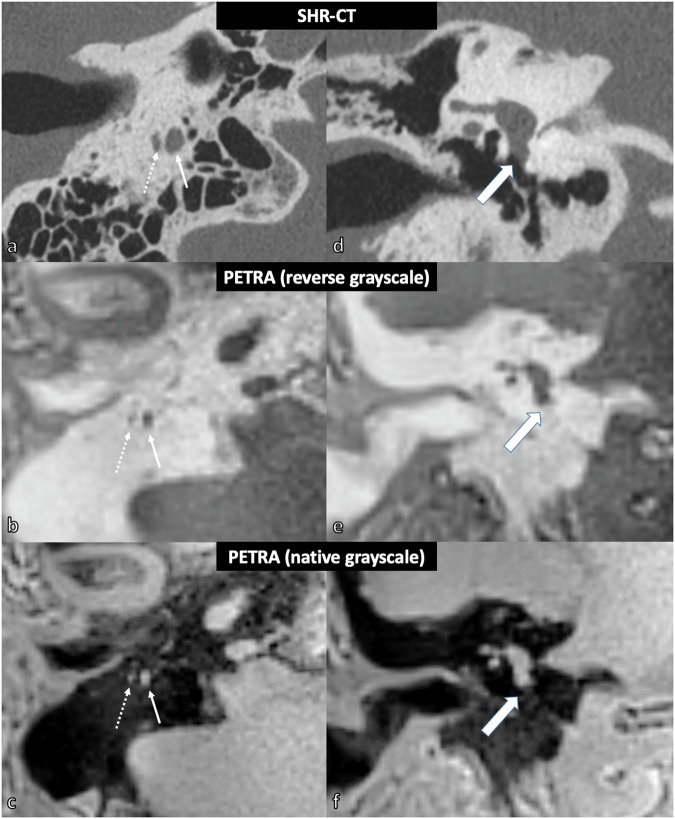

Results: The facial nerve was always clearly visible (score ≥ 2) in the MRI, NR-CT, and SHR-CT scans (p ≥ 0.621). However, the chorda tympani nerve (CTN) was clearly visualized in UTE, STARVIBE, and PETRA sequences in only 33% (2/6 specimens, p = 0.016), 50% (3/6 specimens, p = 0.038), and 83% (5/6 specimens, p = 0.017) of cases, respectively, whereas it was always clearly visualized in SHR and NR-CT (p = 0.426). The round window (RW) was never visualized in MRI sequences (p ≤ 0.010), whereas it was identified in all cases in SHR and NR-CT (p = 1.000). There was a strong correlation between measurements obtained from MRI and CT modalities (ICC ≥ 0.837).

Relevance statement: CT-like MRI sequences can image the anatomy of the facial recess and the length of the basal turn of the cochlea with similar accuracy as conventional CT, although they cannot image the round window.